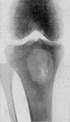

АБСЦЕСС БРОДИ: поражаются метафизы| больших|великих| трубчатых костей (б/берцовая кость - 80%) в детском или юношеском возрасте. Рентгенологически: полость диаметром 2-3 см с четким контуром, часто окруженная остеосклерозом; секвестр и периостит отсутствуют.

Рис..17. Абсцесс Броди.